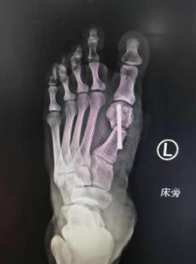

术前

27岁的小徐,7年前出现左足踇外翻畸形,一年前行走时感觉疼痛,反复发作,发展到轻微跛行,这对于爱美的小徐难以接受,前来就诊。

门诊医生给小徐检查,左侧前足变宽,第1跖骨头内侧突出,诊断为左足踇外翻畸形(中度),石院长团队经过讨论,决定采用微创踇外翻技术为其矫形。

术前设计(左图)术中(右图)

术后

第二天,石荣剑副院长徐明亮主任袁罕医生团队为患者进行了左足踇外翻截骨矫形手术,采用低频超声骨刀微创截骨,螺钉内固定,骨刀微创、精准,能更好地保护骨骼血运,使得截骨处更快愈合,手术效果理想,术后第二天患者就下地行走。小徐说脚下轻松了许多,称赞sararz足踝科的技术名不虚传。